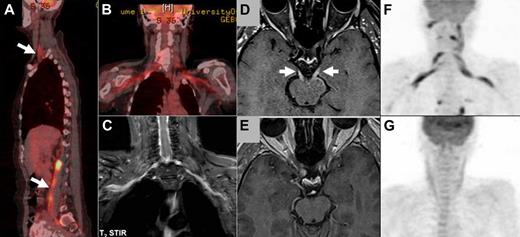

Imaging studies in NL. (A-B) FDG-PET imaging of a patient with neurolymphomatosis (NL). (A) Multiple sites of involvement, including the brachial and lumbosacral plexi (arrows). (B-C) Bilateral involvement of the brachial plexus in the same patient clearly detected by both FDG-PET (B) and by MRI (C) T2 short T1 inversion recovery imaging. (D-E) Enhanced MRI imaging (T1-weighted with gadolinium) of a patient with NL that affected multiple cranial nerves. (D) Bilateral abnormal enhancement of the oculomotor nerves that corresponded to the clinical presentation of bilateral ophthalmoplegia. (E) Complete resolution of abnormal enhancement after 2 cycles of treatment with intravenous high-dose methotrexate and intra-CSF treatment with cytarabine. These imaging findings matched the marked neurologic improvement observed under treatment. (F-G) FDG-PET imaging of a patient with NL who presented with severe painful sensorimotor neuropathy and bilateral brachial plexus involvement. (F) FDG-PET findings at diagnosis of NL compatible with bilateral brachial plexus involvement by lymphoma. (G) Complete resolution of abnormal tracer uptake after 2 courses of treatment with systemic high doses of methotrexate and cytarabine. The treatments lead to clear neurologic improvement and good control of the painful neuropathy.

The response to treatment was assessed by comparing the pretreatment and posttreatment scores of ECOG-PS, neurologic function score, report of neurologic status, and objective response as detected by imaging. Of the 47 treated patients, pretreatment and posttreatment evaluations were available as follows: ECOG-PS and neurologic function in 35 patients, detailed neurologic status in 28 cases, and imaging in 25 patients. Response to treatment based on 35 pretreatment and posttreatment evaluations was noted in 16 (46%) patients who presented with a complete or partial resolution of their symptoms and signs. An additional 9 (26%) patients stabilized on treatment, and the remaining 10 patients progressed despite treatment. The median ECOG-PS changed from 2 (pretreatment) to 1.5 (posttreatment) and median neurologic function score from 2 to 1. These changes were not statistically significant (paired t test). Posttreatment imaging demonstrated complete resolution of the previously documented abnormalities related to NL in 14 (56%) of 25 patients (Figure 1D-G), partial response in another 3 (12%) cases, 1 patient showed no change, and 7 (28%) worsened. Objective response as demonstrated by imaging corresponded to clinical and neurologic improvement in all 17 patients.

Of all diagnostic tools, imaging studies are of the greatest clinical utility. All our patients were evaluated by one or more imaging techniques, the majority (94%) by MRI. MRI reveals nerve or root enlargement with or without contrast enhancement and often involvement of neural plexus (brachial or lumbar) that is more difficult to detect1,7-14 (Figure 1C). MRI findings are not specific for NL and might sometimes be seen in acute or chronic inflammatory radiculoneuropathies, in neurofibromatosis, in inflammatory pseudotumor, and in malignant tumors of the peripheral nerve sheath. Interpretation of imaging studies in the context of clinical manifestations and laboratory studies is necessary. MRI yields abnormal findings in almost 80% of affected patients (Table 2) and facilitates the diagnosis, particularly when a history of hematologic malignancy is known.

PET-CT appears to be a highly sensitive diagnostic method facilitating identification of NL based on our experience and that reported in the literature (group B, Table 2; Figure 1A,B,F). Altogether, the reported experience is of 40 NL patients evaluated by PET-CT, among whom 87.5% were positive studies. Although the total number of reported cases diagnosed by PET-CT is still small, positive findings are highly suggestive of the diagnosis of NL, particularly in patients with a known history of hematologic malignancy. Together with MRI findings, PET-CT may define the best target for a biopsy, if one is indicated, especially in the instance of primary NL.

Clinical improvement (functional recovery, reduction of pain) and radiographic resolution (improvement of nerve root enlargement and enhancement or normalization of FDG-PET uptake) have been observed in 50% to 70% of treated patients (Table 2; Figure 1D-G). Standardized criteria to measure response are not available; therefore, no recommendations can be made regarding treatment response.